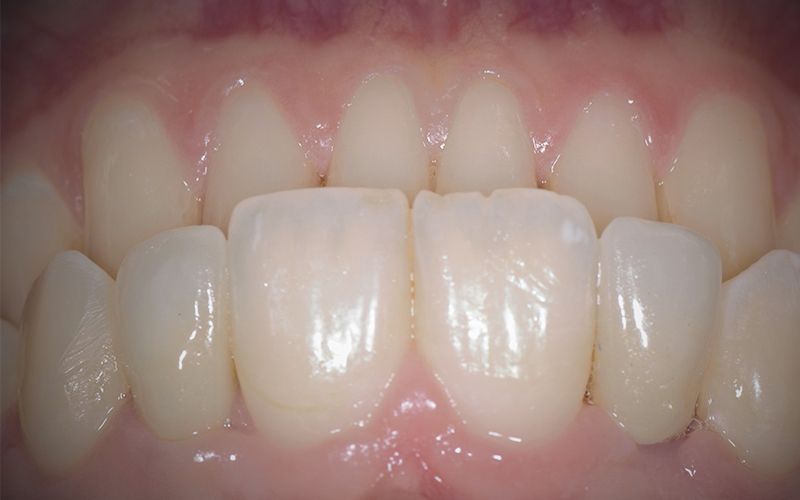

Las coronas de zirconio monolítico fresado con cut-back iban cementadas sobre dos bases de titanio previamente talladas para salvar el eje de inserción de los implantes.

Al cabo de unos días se hicieron los controles clínicos y radiológicos pertinentes y se procedió a cementar las dos coronas de forma definitiva dando por finalizada la rehabilitación por agenesia de los dos incisivos laterales 12 y 22.